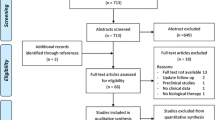

A total of 1325 articles were identified from the databases. A total of 141 studies were removed for duplication, and then, 729 studies were screened because they were correspondence or technical notes or irrelevant studies. A total of 317 studies were excluded because they were based on animal models or cadaver species, biomechanical studies and reviews. A further 85 non-controlled trials were also excluded. Twenty-seven trials were excluded from the remaining because their augmented interventions were not stem cells or not only stem cells. Of the remaining 26 studies, five were not in English, two did not have suitable clinical outcome, and one was not available in full-text articles, and therefore, they were also excluded. After the application of exclusion criteria, a total of 18 papers, all in English, were included in this meta-analysis (Fig. 1) [10, 23,24,25,26,27,28,29,30,31,32,33,34,35,36,37,38,39]. All selected studies used a conventional parallel group design, comparing CD versus CD plus stem cell therapy. Of the 18 identified studies, 11 studies were randomized controlled design [10, 28,29,30,31,32,33,34, 37,38,39], and the other 7 were retrospective studies [23,24,25,26,27, 35, 36].

Figure 2A, B illustrated the quality of each RCT. Table 1 indicated the quality of the 7 included retrospective studies.